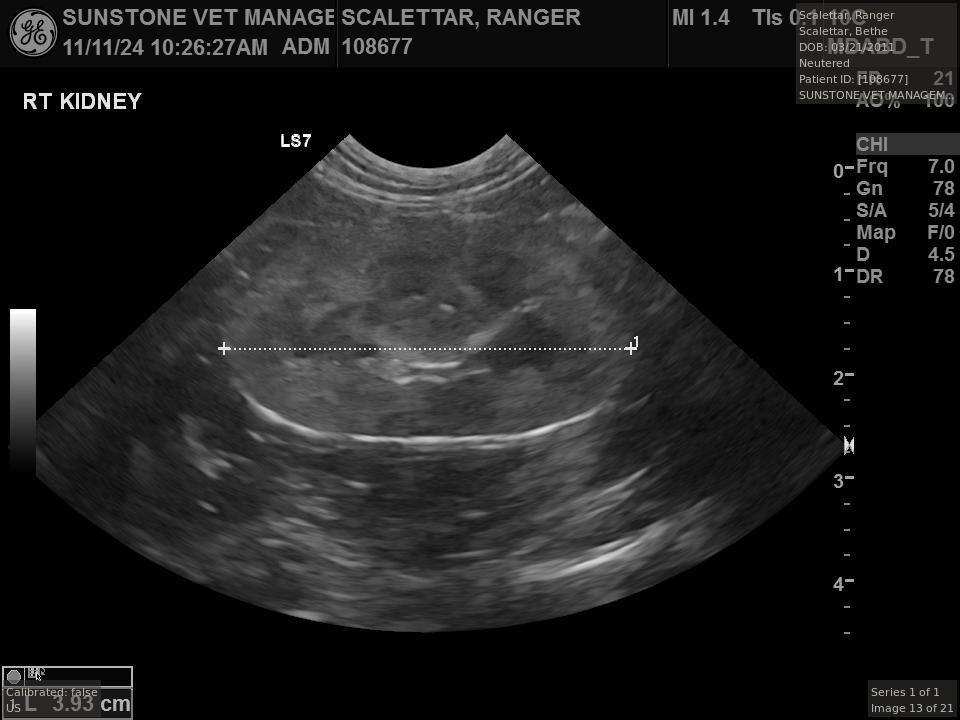

Veterinary Examination

This study describes a visit to a veterinary specialist with a cat suffering from small cell lymphoma. The visit included both X-ray and ultrasound examinations.